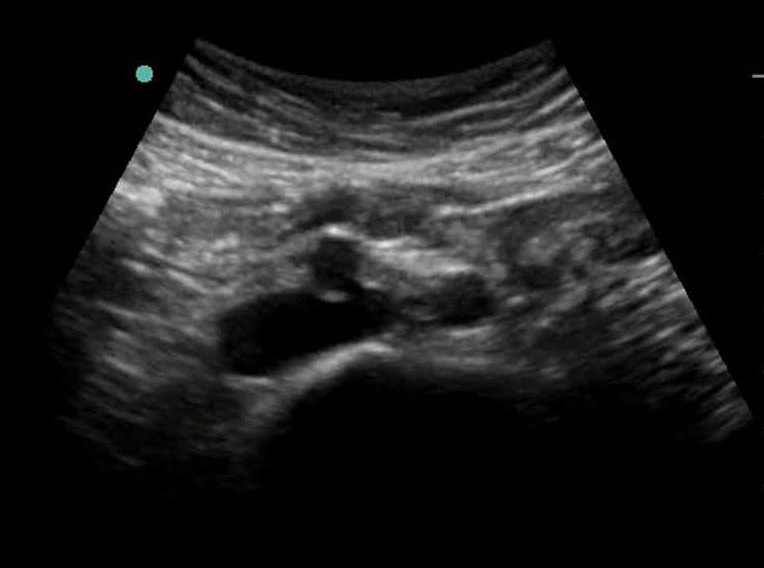

Bifurcación de aorta distal - Imagen transversal